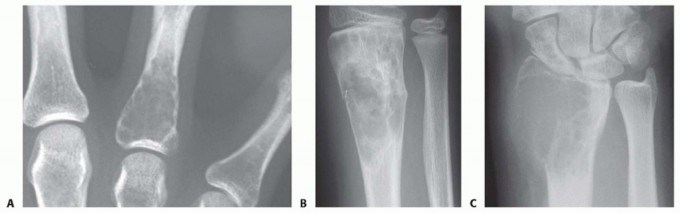

Treatment of Enchondroma, Bone Cyst, and Giant Cell Tumor of the Distal Upper Extremity